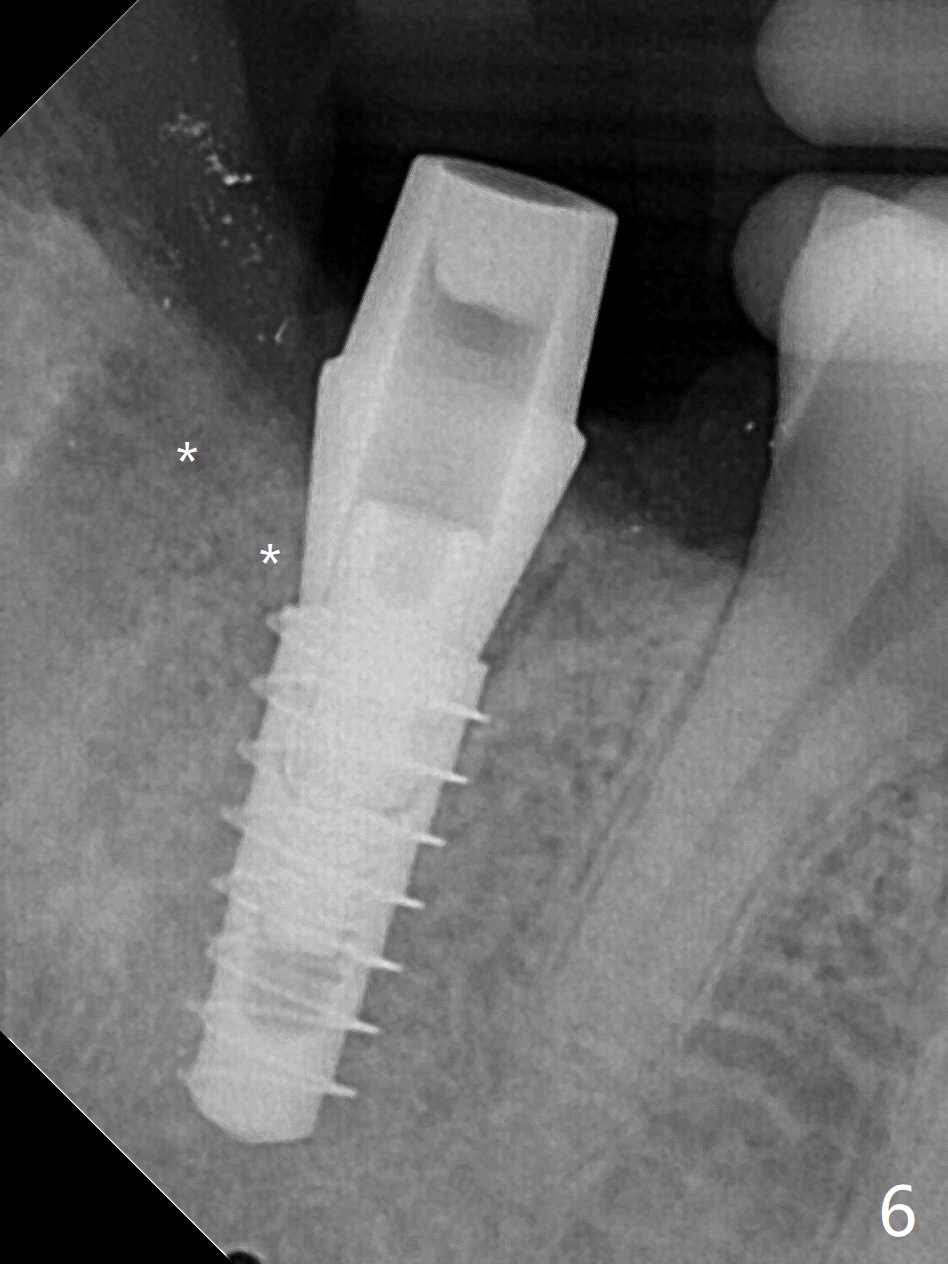

36岁女,右下第二磨牙颊侧瘘道,近中牙槽窝(图一:M)离下牙槽神经远,将是种植位点。图二是该牙CT3维横断面,显示近中(M),远中(D)牙根之间颊侧(L: 舌侧)连接(*);牙齿拔除后,牙槽窝成C型(图三,面对舌侧);由于颊侧骨板(图四:B)中断,缺损,植体将植入近中舌侧牙槽窝(绿色,导板)。优点便是三面骨质包绕(rao,图五),只有颊侧需要大量粘性骨粉(图六:*)。